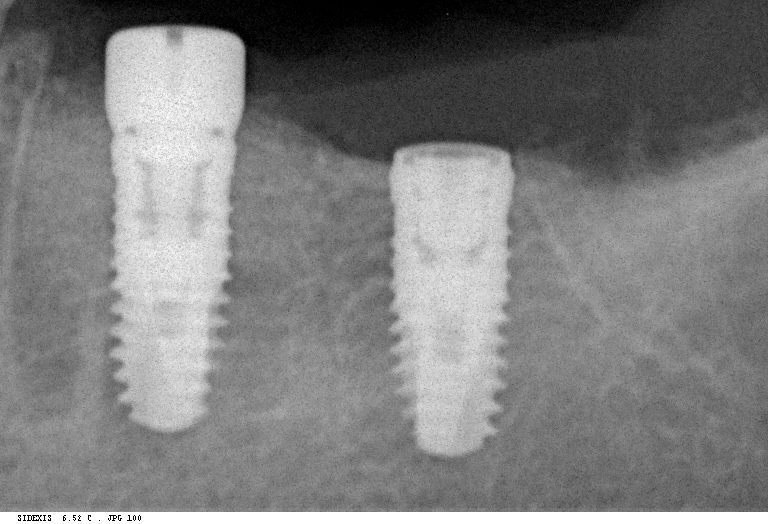

Исследование на рентгене после имплантации зубов

Раздел: Снимки-откровения